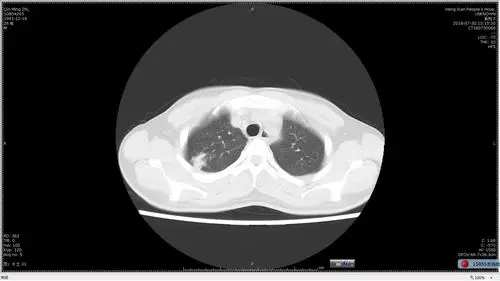

性肺结核-/上中下 涂(-)进展期,初治 写美篇 比较典型的肺结核病灶

多发小结节状卫星灶的肺结核

空洞型肺结核ct图

典型急性粟粒性肺结核